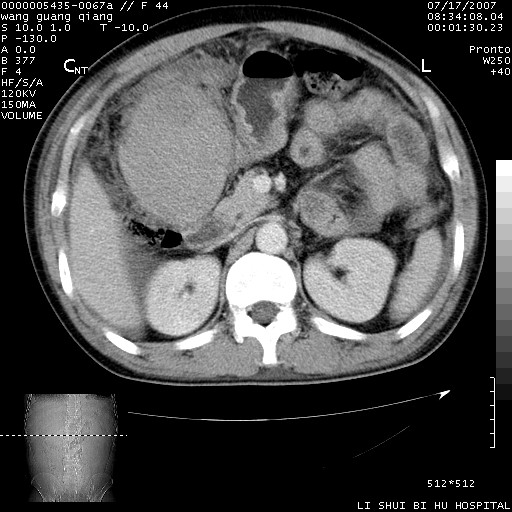

以下是引用dyqct在2007-7-18 10:46:00的发言:[br]胆囊明显增大,壁增厚,明显强化;后下方见大片高密度区,ct值68hu,无强化,周围见多数条纹状高密度影,边界不清。双膈下间隙、肝肾隐窝见带状及片状低密度区。[br]右侧胸壁后缘亦见新月形水样密度区。[br]考虑:1、急性胆囊炎伴周围出血;[br] 2、少量腹水、右侧少量胸腔积液。[br][br][本贴已被 dyqct 于 2007-7-18 10:48:47 修改过]